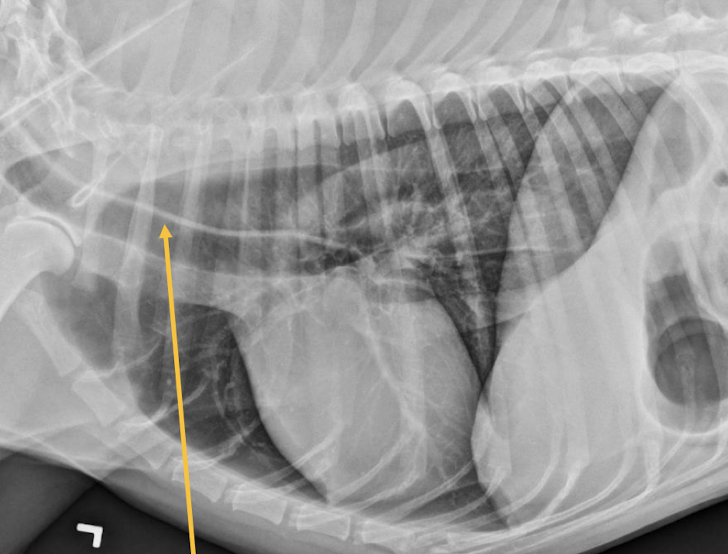

A

Esophageal dilation

Arrow = tracheal stripe